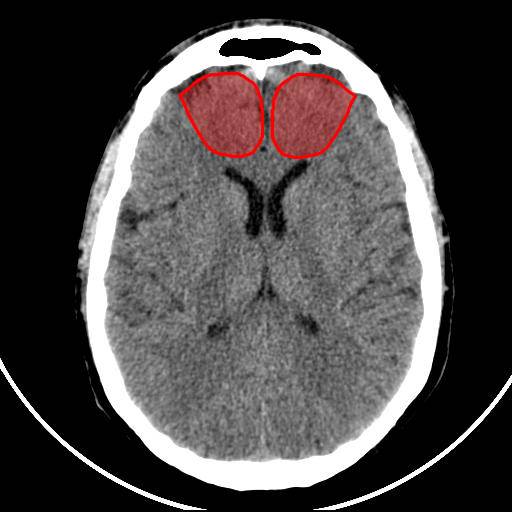

Analyse quantitative

Territoire de l’artère cérébrale antérieure